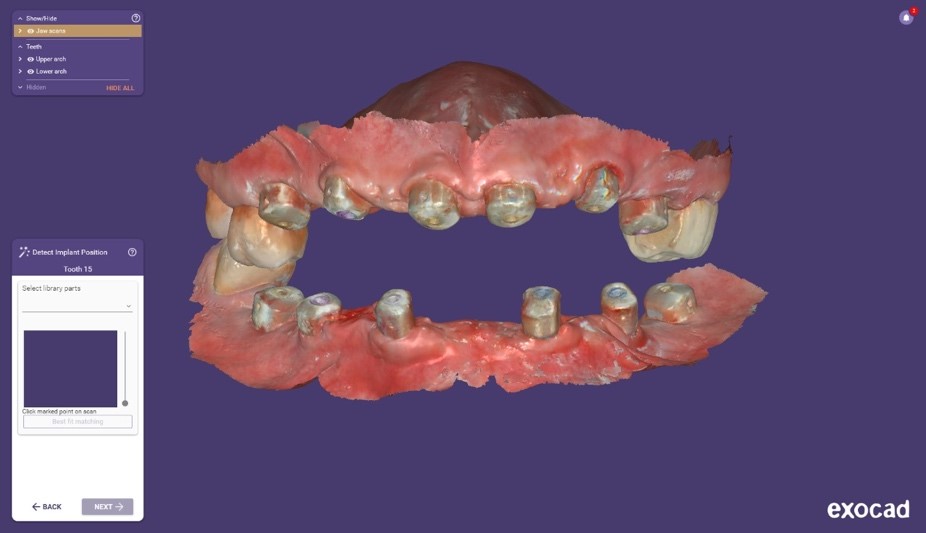

Si procedeva quindi alla scansione degli iPhysio® utilizzando uno scanner intraorale (IS 3600®, Dexis, Envista Holding Corporation, Brea, USA) (Fig. 4 a). Inviavamo i file STL al laboratorio odontotecnico per progettare e realizzare la protesi finale (Fig. 4 b,c,d,e,f).

Progetto CAD finale

Fig. 4(a)

Progetto CAD finale 2

Fig. 4(b)

Progetto CAD finale 3

Fig. 4(c)

Progetto CAD finale 4

Fig. 4(d)

Progetto CAD finale 5

Fig. 4(e)

Progetto CAD finale 6

Fig. 4(f) Progetto CAD finale della protesi.

Il laboratorio odontotecnico utilizzava le più recenti tecnologie CAD/CAM per produrre una protesi dentale personalizzata e di alta qualità che si adattasse perfettamente e garantisse funzionalità ed estetica ottimali. Il concetto iPhysio® facilita il recupero automatico del profilo di emergenza sottogengivale da parte dell'odontotecnico per la realizzazione di soluzioni personalizzate sia con la protesi cementata che con la protesi avvitata (Fig. 5 a,b,c). La paziente tornava per il posizionamento del restauro finale in zirconio avvitato (Fig. 6 a,b).